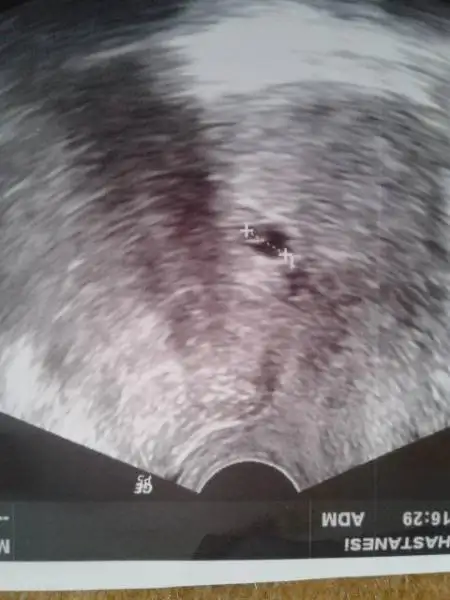

2. Ve 3. Başka bi Dr. Ilki karindan 2.si alttan 2 kese gördü içleri boş, boş gebelik haftaya kadar zaman verelim olmazsa alalım dedi

sonra saat 11 de diğer özel hastaneye gittim.daha önceki kese ölçümlerimi söyledinm çok az ve yavaş büyüyor bu anormal dedi baktı baktı ne kalp atışı olabilir ne yok sac ne embriyo hiçbişey yok dedi.ben alttan bakın lütfen dedim alttan baktı hiçbişey yok bu büyüklükte kese nasıl boş olabilir almamız lazım ama kestirip atmış olmayalım mucize bekleyelim bi haftaya bişey görmezsek haftaya salı alalım dedi

ya valla kafam allak bullakhatta ekranda daha belirgin embiryo resmi vardı da resim de pek belli de olmuyor.peki aynı gün başka bir doktorun alttan hiçbişey görmememsi ve alalım demesi